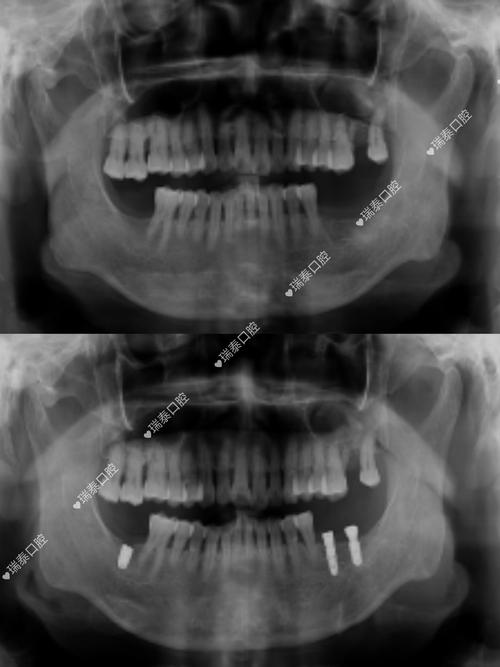

种牙前是否需要拍片,是许多准备接受种植牙手术的患者关心的问题,从临床实践来看,拍片不仅是必要的,更是保障种植牙成功和安全的关键环节,种植牙手术并非简单的“种螺丝”,而是需要通过精准的影像学检查,全面了解患者的口腔内部情况,从而制定个性化的治疗方案,避免术中损伤重要解剖结构,确保种植体能够长期稳定存在于牙槽骨中。

种植牙的核心原理是将人工种植体(相当于人工牙根)植入牙槽骨内,通过骨结合实现与骨组织的融合,再在上方安装牙冠,恢复牙齿的形态与功能,这一过程对牙槽骨的条件、周围解剖结构的要求极高,而拍片正是获取这些关键信息的“眼睛”。

评估牙槽骨的质量与数量是拍片的核心目的之一,牙槽骨的高度、宽度、密度直接影响种植体的稳定性和长期成功率,缺牙后牙槽骨会逐渐萎缩,若骨量不足,可能需要植骨或上颌窦提升等额外手术;若骨密度过低(如骨质疏松严重),种植体与骨的结合效率会降低,甚至导致失败,通过影像学检查,医生可以准确测量骨量,判断是否具备直接种植的条件,或需要何种骨增量方案。

规避神经血管损伤风险至关重要,颌骨内分布着重要的神经(如下牙槽神经)和血管(如上颌窦血管),若种植体植入位置不当,可能损伤这些结构,导致下唇麻木、出血等并发症,拍片能清晰显示这些解剖结构的位置和走向,帮助医生规划种植体的植入角度、深度,确保安全区域。

排查口腔潜在病变也是拍片的重要作用,患者可能存在牙根残留、囊肿、炎症、骨化性纤维瘤等问题,这些病变若术前未被发现,可能影响种植体愈合,甚至导致手术失败,拍片能帮助医生全面评估口腔健康状况,必要时先进行治疗再进行种植。